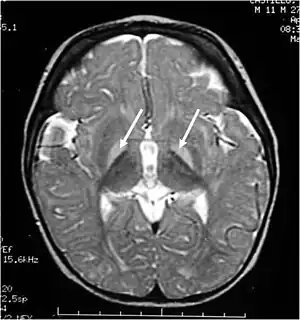

Extremely high levels of unconjugated bilirubin in plasma enables bilirubin to cross the blood-brain-barrier to reach the brain and central nervous system to impart damage. This is termed kernicterus, or bilirubin encephalopathy. Kernicterus is rare in adults but is prevalent in newborns with underdeveloped blood-brain barriers and lower albumin binding capacities, which otherwise buffers excess bilirubin in adults. To date, only 4 such cases have been published, with 3 of them associated with CN-2, the milder form of the syndrome.[28][29] The risk of developing kernicterus in CN-2 patients increases during physiological stress, such as prolonged fasting or anaesthesia.[30] In infants, a bilirubin-albumin molar ratio of >0.8 reflecting insufficient bilirubin binding is considered at risk of developing kernicterus but the indicative value in adults remains unclear.[31]

Unbound plasma bilirubin past a threshold exerts neurotoxic effects through triggering diversified metabolic cascades. It decreases oxygen consumption and increases neuronal apoptosis directly or indirectly through release of pro-inflammatory enzymes by glial cells.[32] Primary targets affected are the basal ganglia, brainstem and cerebellum due to differential tissue binding, bilirubin uptake and cell's higher sensitivity to injury.[32][33]